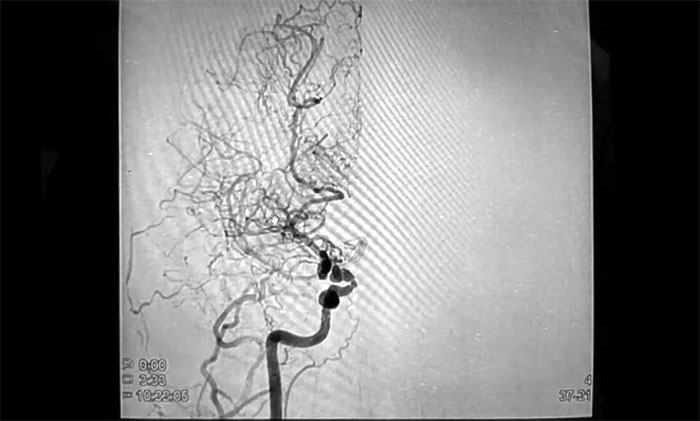

2021年4月,由于头晕症状较前明显加重,胡女士在当地医院行磁共振血管造影(MRA)检查时,被告知脑部有异常血管网,疑似患上了“烟雾病”。

随后,住院行数字减影血管造影(DSA)后,明确诊断为“烟雾病、颅内多发动脉瘤”,这着实把她吓得不轻。

烟雾病,因颅底异常血管网在脑血管造影图像上形似“烟雾”而得名,是一种病因不明的、以双侧颈内动脉末端及大脑前动脉、大脑中动脉起始部慢性进行性狭窄或闭塞为特征,并继发颅底异常血管网形成的一种脑血管疾病。

▲烟雾病可致缺血性和(或)出血性卒中发生

在这一迫切心理下,经亲友推荐,胡女士来到上海蓝十字脑科医院,以寻求进一步治疗。宫卫东主任及神经外科6A病区专家团队为胡女士完善了相关检查,头颅CTA示:右侧大脑中动脉主干节段性狭窄,中远段分支明显减少,近乎全部闭塞;局部见代偿性微细分血管网,符合烟雾病特征。颅内动脉环区多发微小动脉瘤。

▲ 右侧中动脉狭窄,异常血管网形成